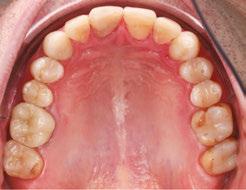

In my practice at Teeters Orthodontics in Peoria, Arizona, I have fully integrated Angel Aligner into my treatment protocols. One of the key innovations I utilize is the angelButton™, a unique feature designed to enhance sagittal bite correction and correct crossbites more efficiently and effectively. By incorporating these built-in buttons with elastics, I am able to achieve more predictable and efficient outcomes for my patients, improving their overall bite alignment with greater precision.